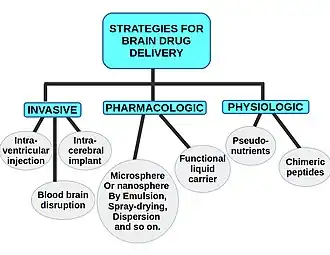

Delivery of molecules

Molecules that enhance the regeneration of neural tissue, including pharmaceutical drugs, growth factors known as morphogens, and miRNA can also be directly injected to the injury site of the damaged CNS tissue. The strategies for brain drug delivery may be widely categorized into invasive (neurosurgical-based), pharmacologic-based, or physiologic-based. The neurosurgical-based strategies contain intraventricular drug infusion, intracerebral implants, and BBB disruption. The pharmacologic-based strategies include the use of particles such as microspheres, nanospheres made by emulsion, spraydrying, dispersion and so on. [65][66]